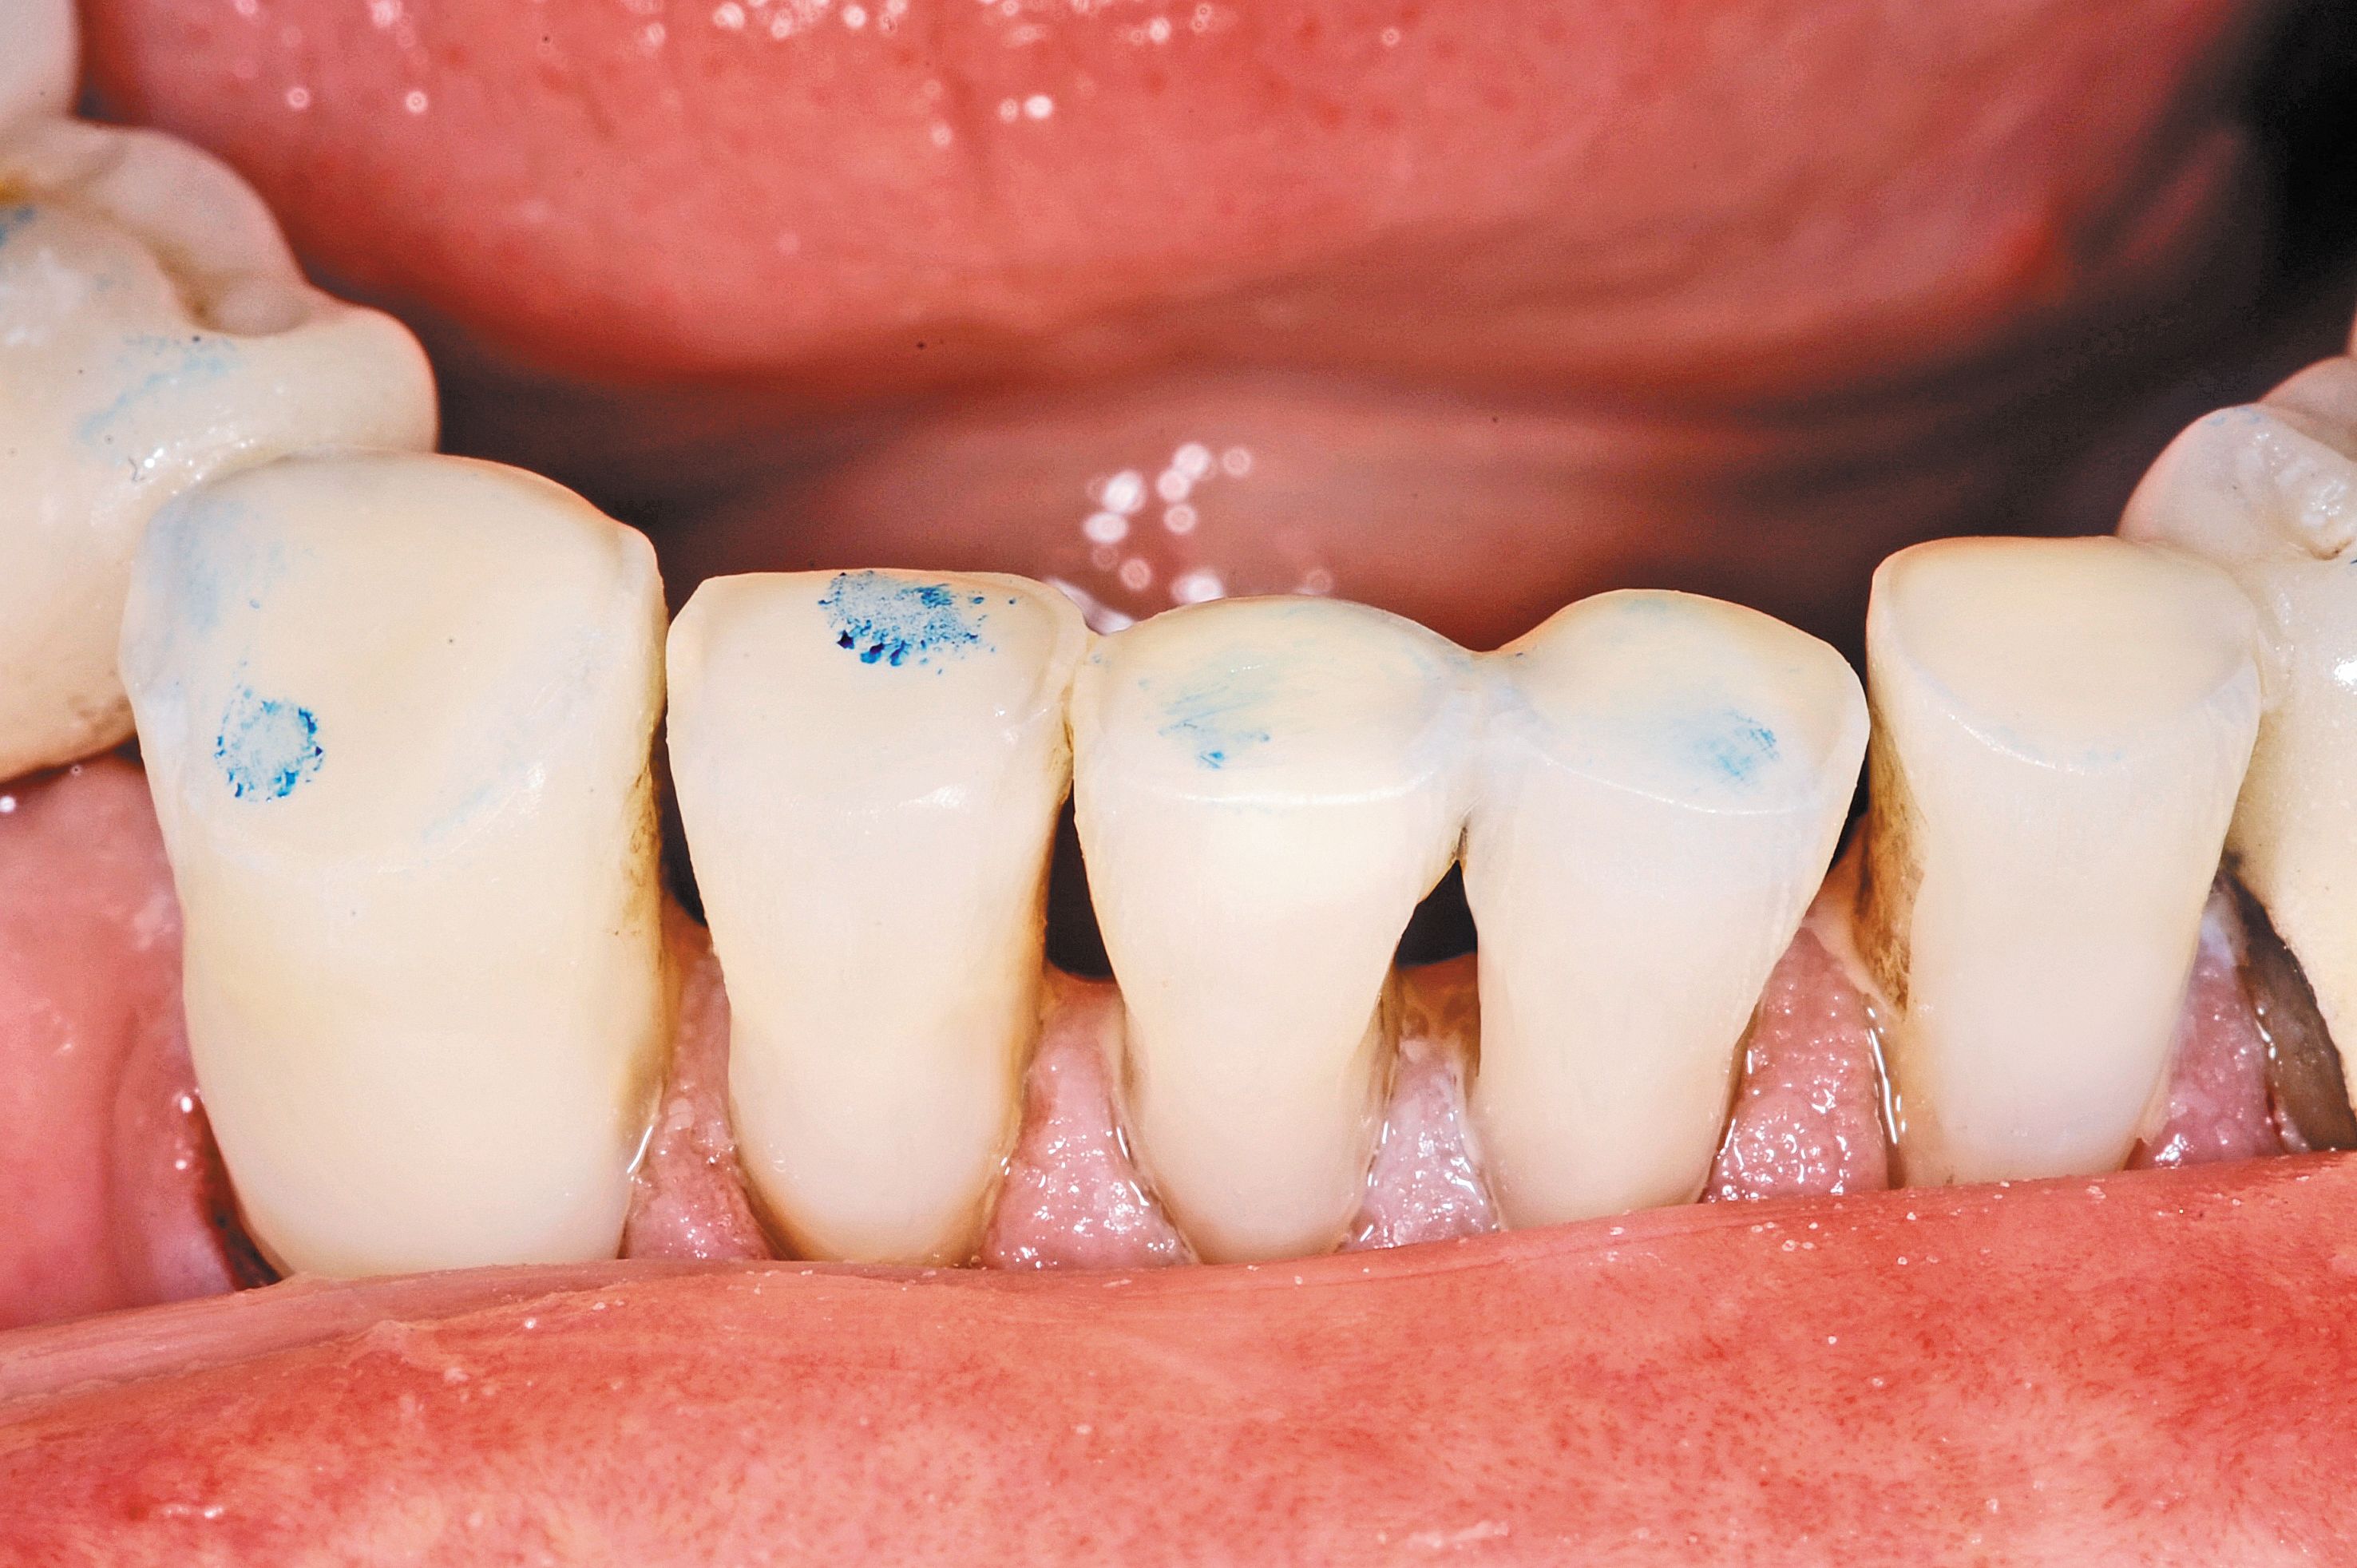

Fig. 4

The conservative nature of this treatment allows for healthy tooth structure to be maintained. By providing for the tooth surface preparation, our goal is 95 percent retention at five years of durable restorations. It must be stressed that no drilling, retention grooves or any other preparation was done at this time outside of micro-abrasion. It seems counterproductive to this practitioner to replace missing tooth structure by drilling away remaining tooth structure.

A selective-etching technique was done by etching only the enamel with 37 percent phosphoric acid for 15 seconds and then rinsed well.

The combination of acid etching of enamel and air abrasion of dentin results in frosty surfaces that provides an improved surface for bonding (Fig. 4). The surface area is greatly increased, and the contaminated outer surface is removed. Occlusal relief does not normally need to be done in these areas as the abrasion of dentin is faster than enamel, resulting in “dished out” areas that “naturally” provide ample clearance.